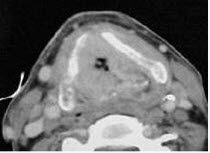

男,55岁,声嘶6年,有长期吸烟史。检查:无呼吸困难。喉镜检查:声带慢性充血,可见右侧声带可见菜花样新生物,右侧声带活动固定,喉部CT检查如下图: